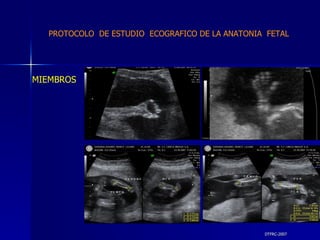

DTFRC-2007 MIEMBROS   PROTOCOLO  DE ESTUDIO  ECOGRAFICO DE LA ANATONIA  FETAL

DTFRC-2007 ECOGRAFIA MORFOLOGICA  HALLAZGOS FRECUENTES   GENITOURINARIA DISPLASIA RENAL MULTIQUISTICA  3 HIDRONEFROSIS  2 QUISTE DE OVARIO FETAL  1 SISTEMA DIGESTIVO DILATACION INTESTINAL  2  SISTEMA ESQUELETICO   PIE BOT  2  20 % 6 % 6 %